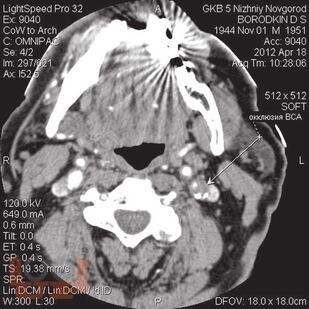

В пособии представлен не только хирургический раздел, но и анатомия кровообращения головного мозга и неврологическая симптоматика цереброваскулярных нарушений при атеросклеротических каротидных поражениях, поскольку каротидная хирургия неразрывно связана с этими аспектами. Приводится алгоритм обследования больных, охватывающий все современные методы нейровизуализации с указанием уровней доказательности, чувствительности и специфичности каждого из них. Особый акцент сделан на ценности ультразвуковых методов, которые наиболее доступны в клинической практике и достаточно информативны. При изложении лучевой семиотики для иллюстрации основных ангиоморфологических изменений даны эходопплерограммы, ангиограммы. Подробно описаны показания к хирургическому лечению, различные методы реконструкции сонных артерий.